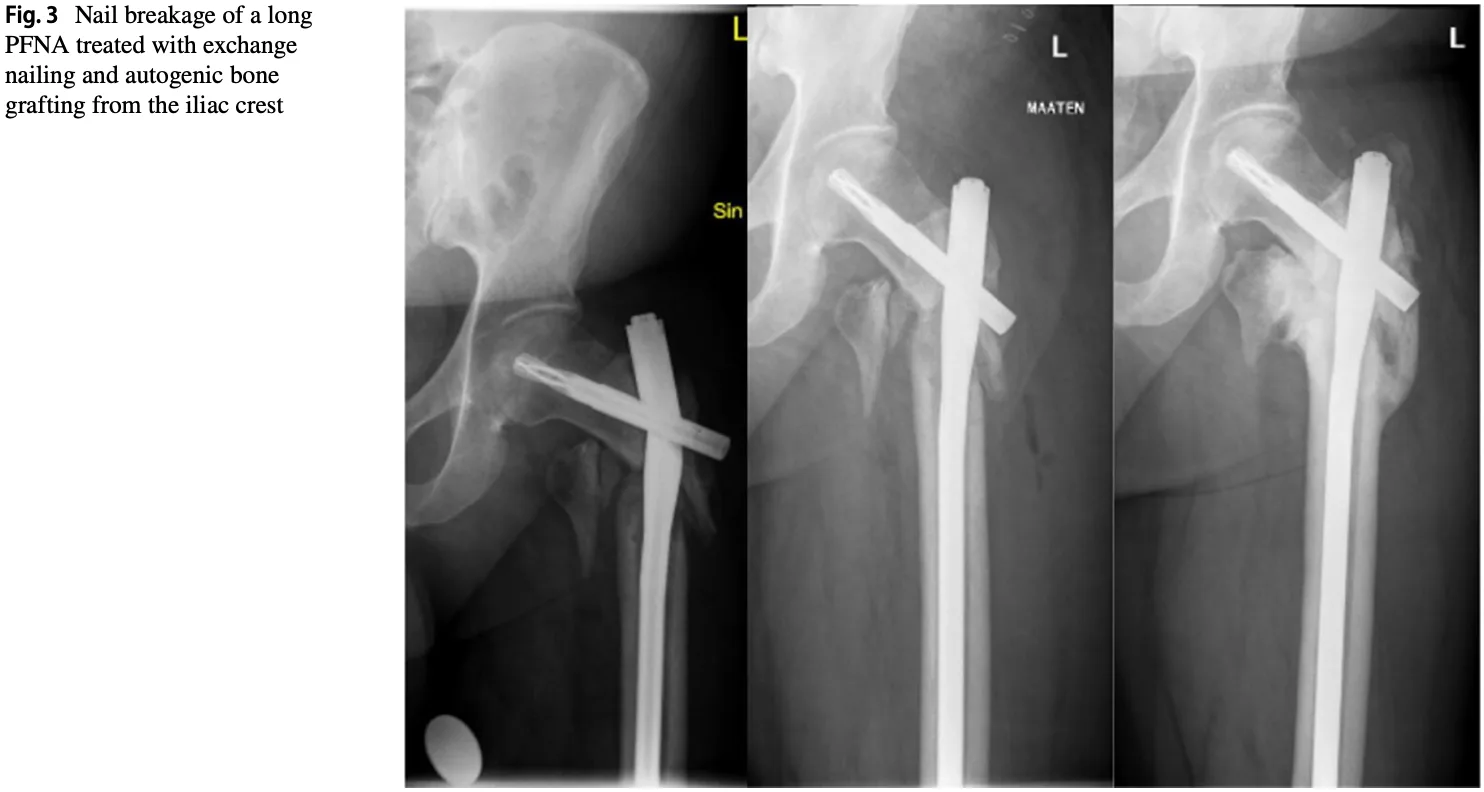

今日来られた事例は, 髄内釘は折れていませんでしたが, 転子下に骨折を生じていました.

引用元:Halonen LM. Peri‑implant fracture: a rare complication after intramedullary fixation of trochanteric femoral fracture. Arch Orthop Trauma Surg. 2022. 142.

X線写真を撮像したところ, 髄内釘が挿入されているにもかかわらず, 大腿骨転子下骨折を認めました.